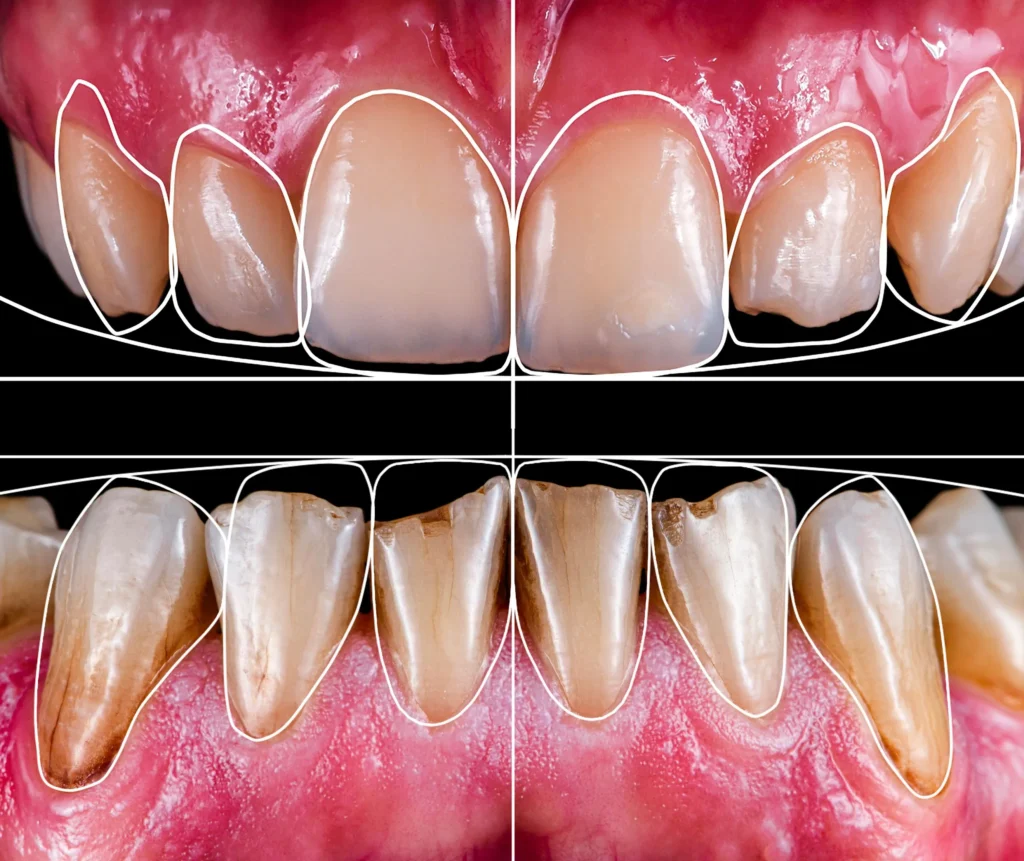

Fase 1. Raccolta delle aspettative del paziente e dei dati accurati, che comprendono fotografie dettagliate del volto e dei denti del paziente, radiografie e scansioni intraorali. Questi dati vengono poi caricati su un software specifico che analizza la posizione, la forma e la proporzione dei denti, il rapporto con le labbra e gli altri tratti del volto.

Fase 2. Match delle scansioni digitali della dentatura del paziente con foto frontali del paziente. Il medico a questo punto, attraverso il software, può creare una simulazione 3D del sorriso ideale e mostrarlo al paziente su monitor.

Fase 3. Alla pre-visualizzazione su monitor segue la prova fisica con mock up. Il mock-up è un provino in resina che consente al paziente di “indossare” la prova del lavoro definito. Si pensi, ad esempio a protesi dentarie o a faccette estetiche. Così facendo è possibile analizzare anche il rapporto tra denti e labbra, l’occlusione dentale e la fonazione. Il paziente può fugare ogni suo dubbio, e se lo ritiene necessario richiedere modifiche.